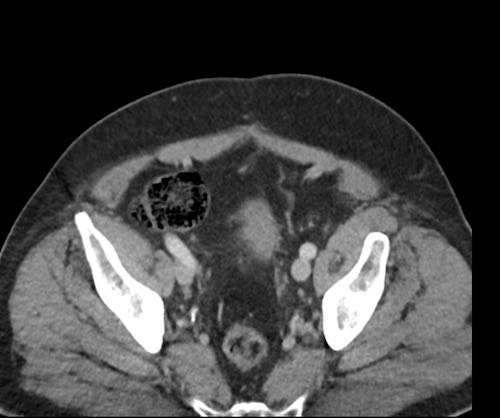

Ca lâm sàng 2

Cuộn qua các lát cắt.

Bạn có thể phát hiện tất cả các tổn thương cấy ghép phúc mạc không?

.jpeg)